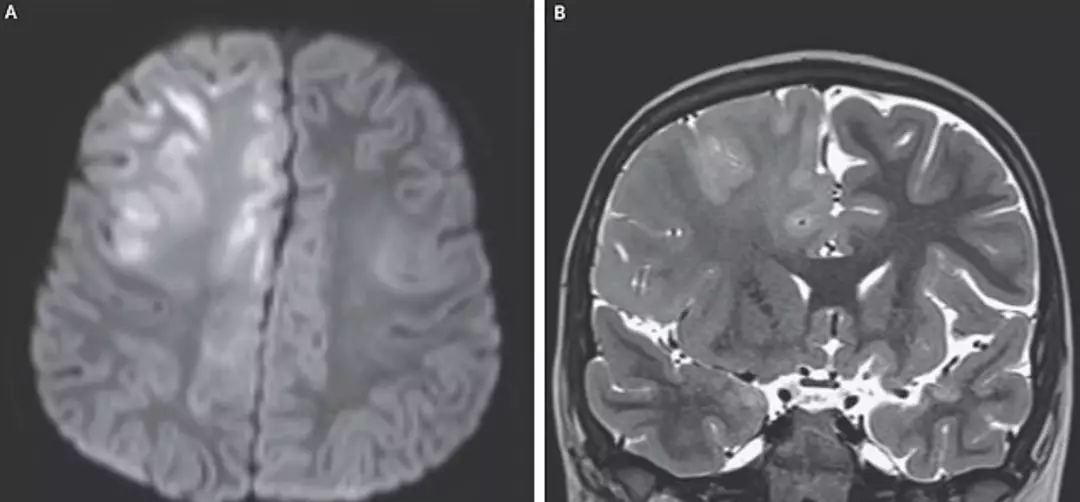

According to reports, the child caught measles at seven months old and was believed to have recovered. Years later, at age six, he began to experience seizures and a decline in cognitive function. Physicians diagnosed subacute sclerosing panencephalitis (SSPE), a progressive brain disorder tied to earlier measles infection.

Encephalitis International notes that SSPE most often starts to appear six to eight years after an initial measles infection and is “related to destruction of the infected brain cells”.